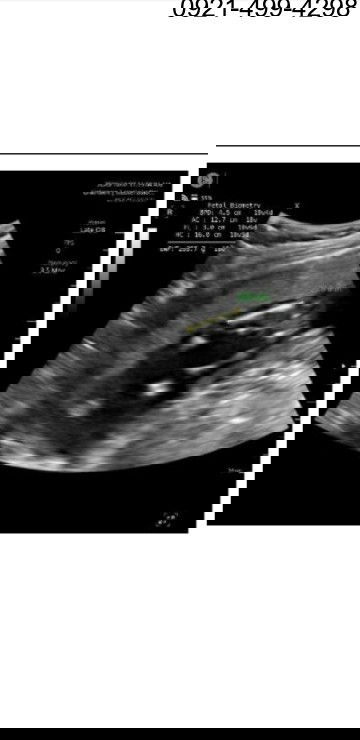

Baka may same po akong ultrasound jan? Boy po ba or girl ito?